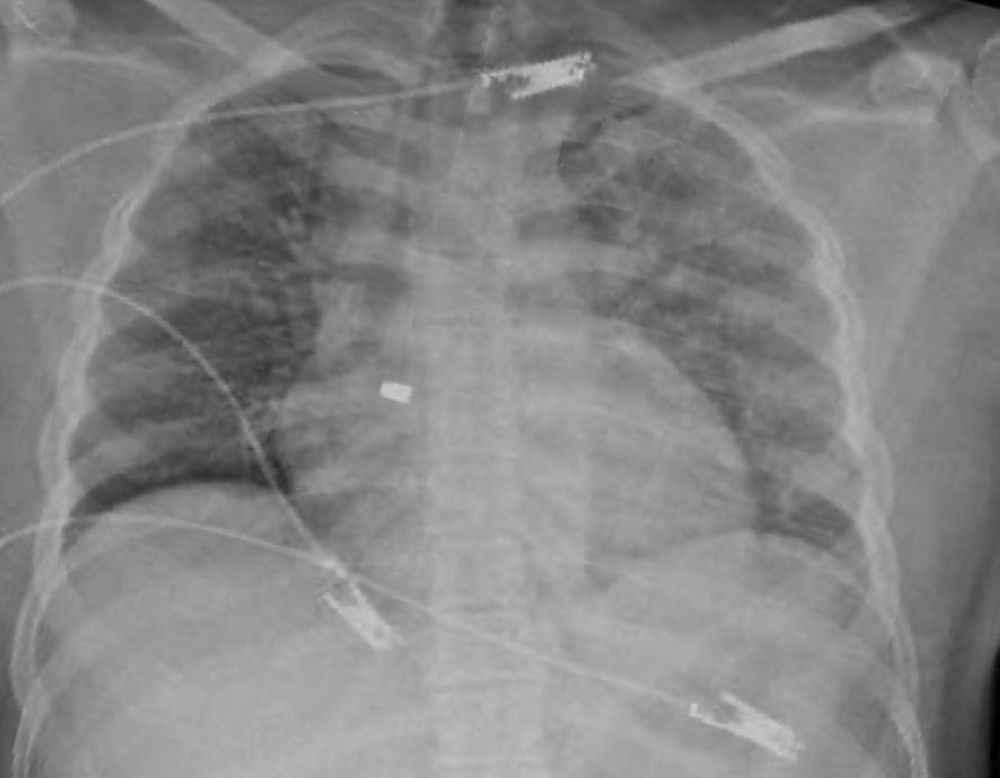

وفي التفاصيل، وصل المصاب إلى مدينة الملك سعود الطبية، في حالة غير مستقرة مع هبوط في الدورة الدموية، وأكدت الأشعة الصوتية وجود تجمع دموي حول القلب؛ مما أدى إلى حدوث الإندحاس القلبي وشلل القلب عن ضخ الدم، وبقيادة استشاري جراحة الإصابات د. طارق السباحي؛ تم نقل المريض بشكل عاجل إلى غرفة العمليات وفتح الصدر وفتح تجويف التامور وإزالة الضغط حول القلب وإصلاح الإصابة في عضلة البطين الأيمن.

تمكنت الجهود الطبية من إعادة استقرار علامات المريض الحيوية، ليتم بعد ذلك التدخل من فريق جراحة القلب لدراسة وجود الرصاصة داخل القلب؛ حيث تبيّن إستقرار الرصاصة في الصمام ثلاثي الشفرات، ليقوم استشاريين جراحة القلب د. حمد الحبيب و د. محمد بكير بإجراء عملية قلب مفتوح للمصاب؛ تم خلالها إزالة الرصاصة بنجاح دون وجود أي مضاعفات، حيث غادر المريض المستشفى خلال أيام وهو بصحة جيدة -ولله الحمد-.